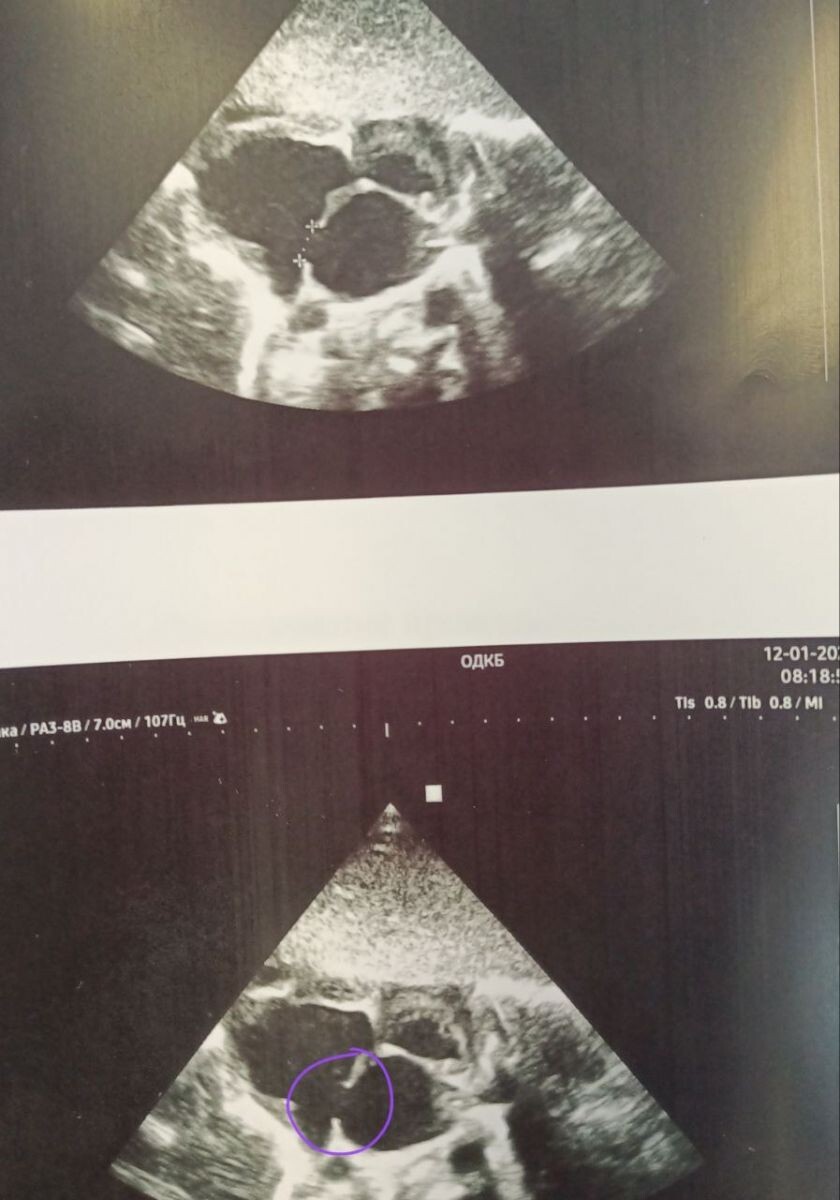

В Областной детской клинической больнице города Владимира проходит лечение новорождённый ребёнок с редкой и сложной сочетанной патологией — множественными пороками развития. По данным ОДКБ, такие случаи требуют одновременной работы сразу нескольких специалистов и тщательной диагностики. С первых дней жизни малыша наблюдают неонатолог, травматолог, невролог, офтальмолог, уролог, хирург и кардиолог. В обследовании также задействованы все диагностические службы больницы: клинико-диагностическая лаборатория, ультразвуковая диагностика, рентгенология и мультиспиральная компьютерная томография. В настоящее время в отделении патологии недоношенных детей № 2 проходит поэтапное обследование и лечение именно такой малыш. У ребенка выявлен целый ряд редких врождённых нарушений: "Множественные аномалии развития шейного и грудного отделов позвоночника(полупозвонки, аномалии количества ребёр, аномалии лопаток, аномалии количества шейных позвонков); Врождённый порок сердца-наличие межпредсердного соо

"Множественные аномалии развития шейного и грудного отделов позвоночника(полупозвонки, аномалии количества ребёр, аномалии лопаток, аномалии количества шейных позвонков); Врождённый порок сердца-наличие межпредсердного сообщения; Аномалия внутренних органов- обратное расположение сосудов портальной системы, дополнительные сосуды печени, дистопия и ротация почки; Другие малые аномалии развития"

(Фото: ОДКБ)